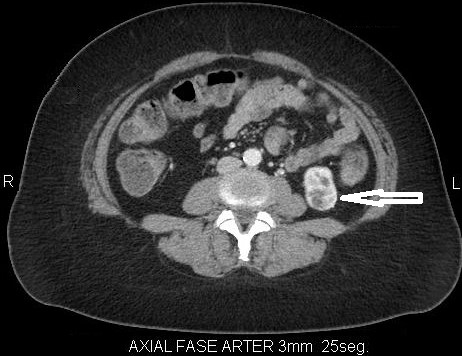

Fase corticomedular y arterial

Esta primera fase ocurre en los primeros 25 a 70 segundos posteriores a la inyección del medio de contraste; la corteza renal, al retener el medio de contraste en este tiempo en los capilares corticales aumenta de una manera intensa diferenciándose de la médula renal, que se encuentra hipodensa.

La fase arterial o corticomedular es esencial para la estadificación, extensión y planificación quirúrgica, si fuese el caso de la neoplasia encontrada, ya que ofrece un mejor detalle vascular (opacificación de los vasos), una mayor definición anatómica y de lesiones vascularizadas en el hígado, el bazo o el páncreas, consideradas dentro del contexto de una metástasis (Fig. 2).

Los errores diagnósticos que pueden presentarse durante esta fase se asocian a lesiones de pequeño tamaño; en el caso de un tumor hipervascularizado pequeño aumentaría su atenuación en la misma medida en que lo haría la corteza. Otro error que puede ocurrir es con los tumores pequeños que se localizan hacia la médula, ya que por su ubicación se mantendrían hipodensos durante esta fase 3-4.